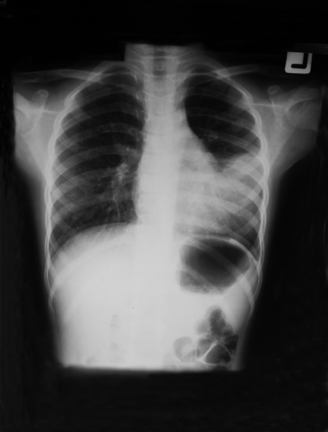

Lung of a child with Respiratory distress syndrome and left sided pneumothorax |